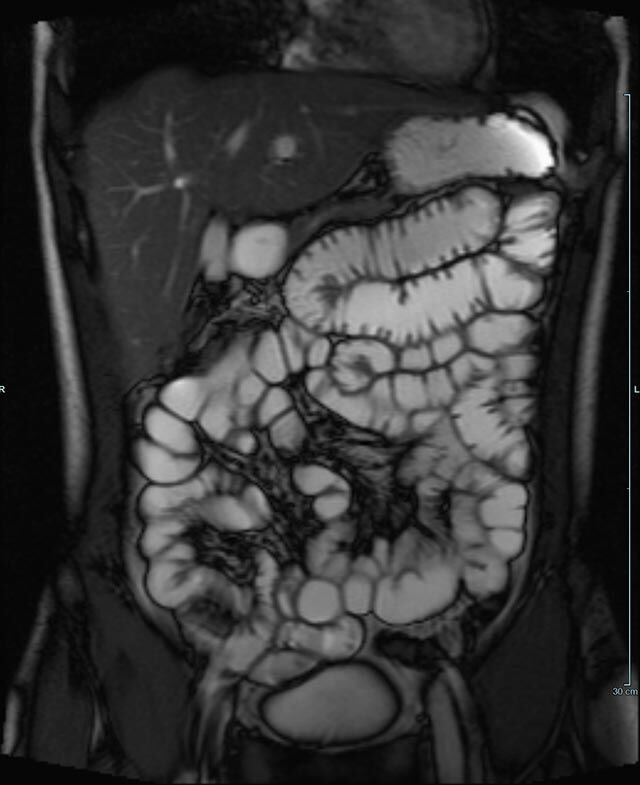

Sellink

• Dünndarm/Dickdarm

• Chronisch-entzündliche Darmerkrankungen wie Morbus Crohn oder Colitis ulcerosa. Beurteilung der Ausdehnung der Entzündung, Darstellung von Fisteln oder Abszessen bzw. einer Passagebehinderung (MR-Sellink, MR-Kolonographie, beide Untersuchungen nach spezieller Vorbereitung)

• Darstellung bzw. Kontrolle im Verlauf bei perianalen Fisteln und Abszessen

• Verlaufskontrolle des Lokalbefundes nach Rektumentfernung bei Karzinom